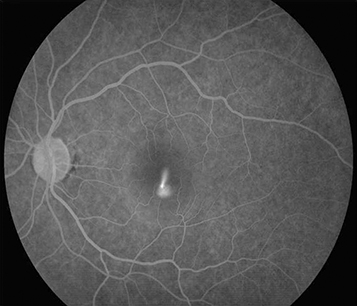

IVFA and ICGA if the diagnosis is uncertain or presentation atypical, CNV is suspected, or laser treatment is to be considered. IVFA shows the nearly pathognomonic smoke-stack pattern of dye leakage in 10% to 20% of cases. ICGA shows multifocal hyperfluorescent patches in the early phase. OCTA is useful for detecting any CNV which can occur secondarily in chronic/recurrent CSCR.